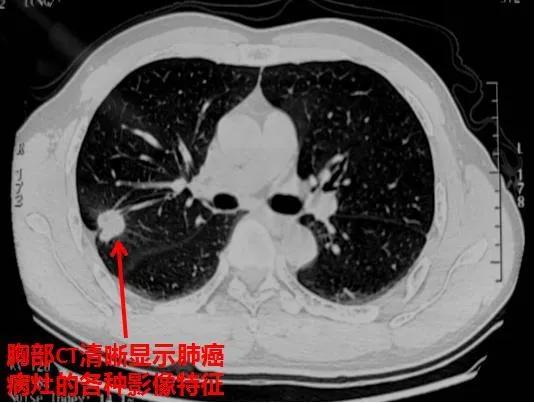

肺结节是指肺部CT检查中发现的直径小于等于3厘米的类圆形或椭圆形影像。近年来,随着低剂量螺旋CT在体检中的广泛应用,肺结节的检出率越来越高。据统计,普通人群中发现的肺结节,恶性比例仅占4%。这意味着,大多数肺结节都是良性的,不必过度恐慌。

早期发现肺结节的关键在于定期进行肺部CT检查。低剂量螺旋CT是目前最有效的肺癌筛查工具,对直径≤1厘米的小肺癌检出率可达80%以上。建议以下高危人群定期进行低剂量螺旋CT筛查: